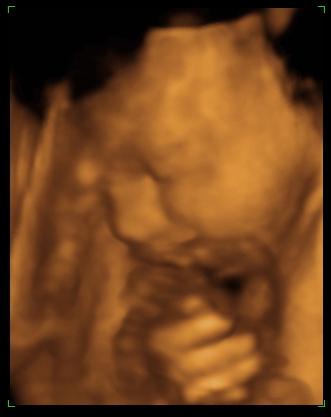

babó hason